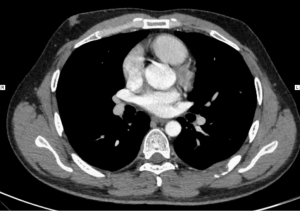

A 34-year-old male was referred to Tianjin Chest Hospital on May 31, 2016 due to persistent stabbing pain in the left chest and back for 45 days. The pain increased after bending, and was accompanied by chest tightness, shortness of breath, and night sweats, with no chills, fever, or fatigue, and no obvious inducements. The patient reported a history of otherwise good health, with no chronic or infectious disease or significant family history. Chest enhanced CT showed an isolated mass on the left chest wall invading the seventh posterior rib, and tuberculosis was initially considered (Figure 1). Tuberculin skin test and sputum smear examination were conducted and the results were negative. A puncture biopsy was further performed, and the pathology was considered to indicate a malignant small round cell tumor, although a hematopoietic tumor could not be excluded. The immunohistochemical results were keratin (−), VIM (+), Ki-67 (+70%), Cal (−), LCA (−), CD117 (−), CD99 (−), CD79a (−), actin (−), desmin (−), SMA (−), and specially stained PAS (−). Immunofixation electrophoresis for urine detection showed no IgG, IgA, IgM, light chain κ, or light chain λ monoclonal components, and there was no obvious abnormality in the bone penetration examination. Nevertheless, due to the increasing severity of the patient’s symptoms, surgical resection was performed to obtain a definitive diagnosis.